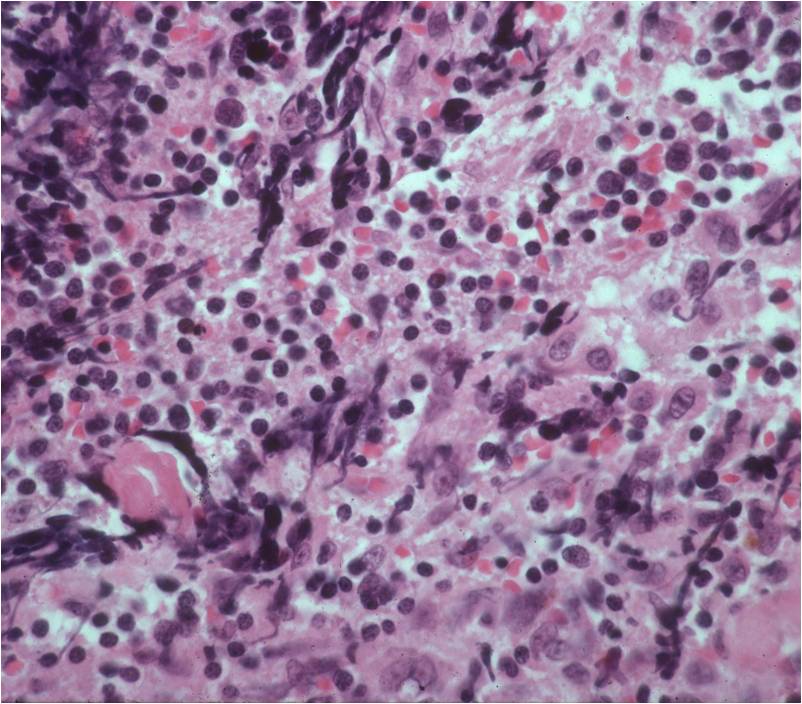

Microscopic Pathology

- Diffuse growth pattern

- Mixture of small lymphocytic cells and larger histiocytic components (Large Malignant B Cells in most cases)

- Cells and no matrix

- Nuclei

- Vary in shape and size

- Grooved vesicular nuclei

- Prominant nucleoli

- Complex reticulin framework

- Prominent fibroblastic component